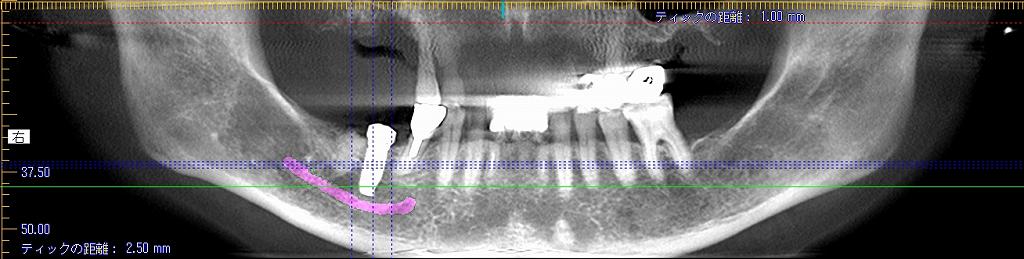

このように5㎜の13㎜というインプラントを埋入しています

隙間には像骨処置として骨補填材を敷き詰めています

このように埋入しています

術前と術後のパノラマになります

しっかりとしたインプラントが埋入できました